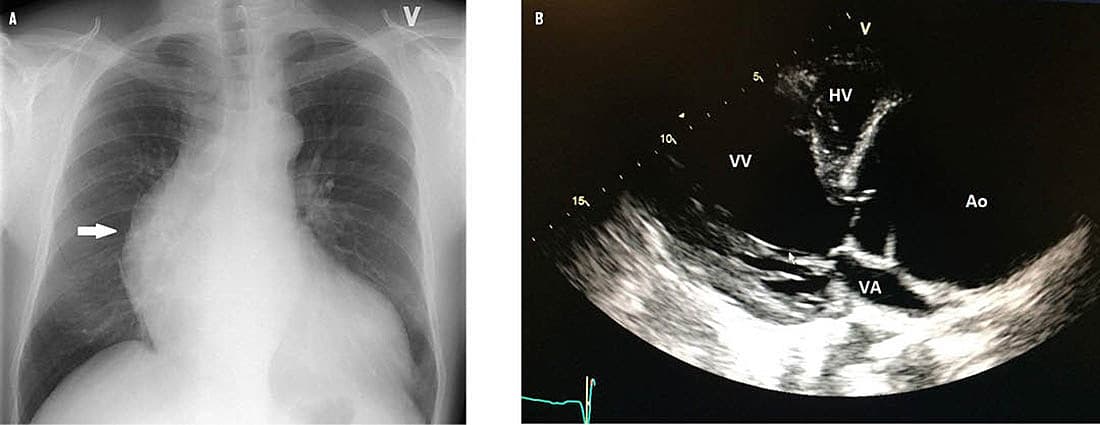

En 40-årig mand henvendte sig til egen læge, idet han igennem seks måneder havde oplevet en udspilende fornemmelse i epigastriet, åndenød, og at musklerne syrede til ved fysisk anstrengelse. Han var ikkeryger og havde hypertension. Som led i udredningen blev der taget røntgenbillede af thorax, som viste betydeligt forstørret hjerte og prominens af aorta ascendens (A). Efterfølgende ekkokardiografi viste en svært dilateret aorta ascendens med en maksimal diameter på 10 cm (referenceværdi: < 3,5 cm), svær aortainsufficiens samt dissektionsmembran i aorta ascendens og arcus (B). Ved en CT af aorta thoraco-abdominalis udelukkede man aneurismer i andre dele af aorta. Han blev overflyttet til en thoraxkirurgisk afdeling med henblik på operation med aortoplastik og indsættelse af rørprotese. Efter en uge blev han udskrevet i velbefindende.